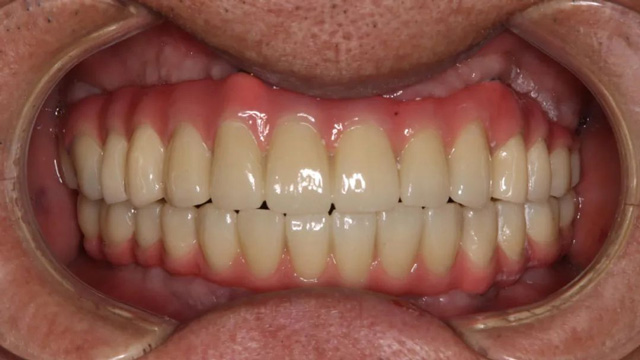

王先生全口種植后戴冠

王先生正式戴牙后